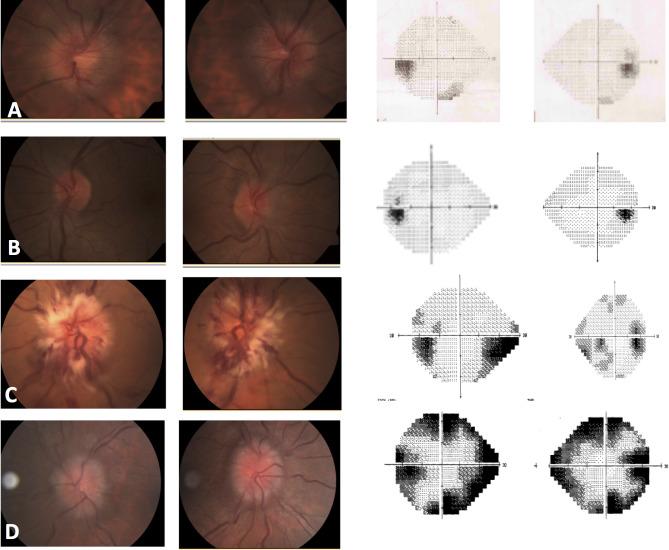

To examine the clinical characteristics and prognosis of occipital tumors that mimic Pseudotumor cerebri (PTC) at presentation due to venous flow obstruction compared to occipital tumors that do not cause venous flow obstruction.

METHODS

The medical records of all patients who presented with increased intracranial pressure symptoms and occipital tumors were retrospectively reviewed. The control group included, an age matched group of patients with occipital tumor who presented due to homonymous visual disturbances, visual hallucinations or incidental homonymous visual field defect but without symptoms of increased intracranial pressure at presentation. Data regarding demographics, ocular presenting symptoms and signs, neurological sings, diagnosis, treatment and prognosis were collected.

RESULTS

At the end of follow up, None of the study group patients, with the exception of one who developed optic disc atrophy and visual deterioration, had visual complaints at the end of follow-up. In the control group, 3 patients had deterioration in the visual field at the end of follow up. Two patients, from the study group, died while in the control group, all patients were alive at the end of follow- up.

CONCLUSIONS

Patients with occipital tumors may present with symptoms similar to PTC secondary to venous drainage obstruction. Therefore, it is important in patients with PTC symptoms and occipital tumor to preform Magnetic-Resonance-Venography or Computed-Tomography-Venography as well. Most of the patients needed surgical intervention in addition to medical treatment in order to preserve visual functions. Probably the early treatment to this group brought to good visual prognosis that was not different from the group without venous drainage obstruction. Therefore, early diagnosis and prompt multi-disciplinary treatment may lead to better results in cases of occipital tumors with venous drainage obstruction.